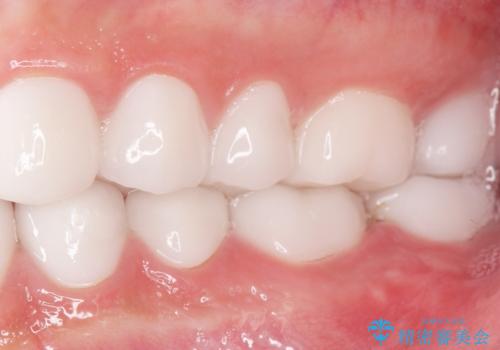

虫歯をしっかりと治療したのち、オールセラミッククラウンによる補綴治療を行いました。

不適なレジン充填によるデコボコがなくなったことで歯磨きしやすくなり、また気にされていた咬み合わせも良くなり、ご満足頂けました。

クラウンの種類:オールセラミッククラウン スタンダード

シェード:NW0